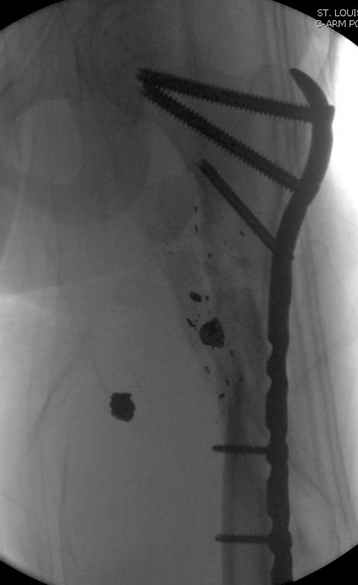

Молодой, с общим состоянием без проблем. Больной соперирован в день поступления и через два дня после операции выписан, так что не успел развиться гной.

Перелом низкоскоростным оружием, типа пистолетного, так что не стали гоняться за пулевыми фрагментами. С нервом пока подождем, иногда нерв восстанавливается если не прямое попадание в нерв, а "сотрясение" (shock wave injury).

Из всех типов фиксации взяли малоинвазивную технику мостовидной пластиной, использовали Locking проксимальную Synthes пластину.

Djoldas Kuldjanov, MD

Department of Orthopedic Surgery

St. Louis University Medical Center